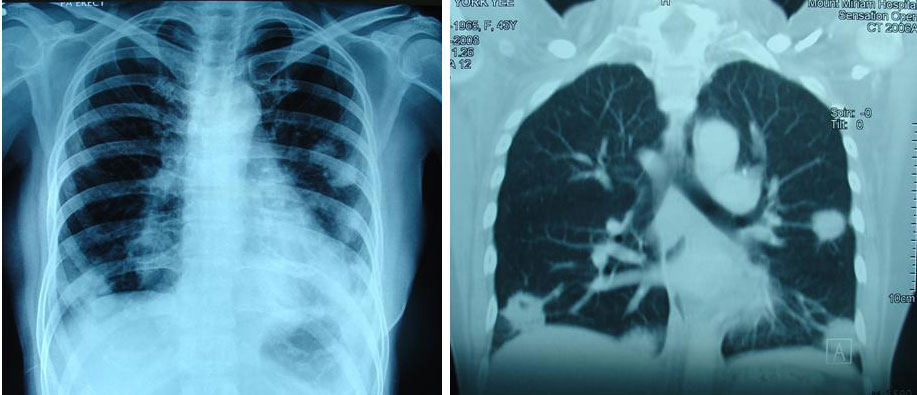

Yee was well for about 9 months. Sometime in January 2007, she noted a swelling in the right side of her neck. A CT scan of the thorax on 19 January 2007 indicated: multiple nodules scattered in both lung fields ranging from 2 to 10 mm. This means the cancer had spread to her lungs.

Yee was given 8 cycle of taxane-based chemotherapy. This treatment was not effective. CT scan on 4 July 2007 showed the nodules in the lungs were progressing.

Yee received more chemotherapy – 6 cycles of Navelbine + Herceptin. This treatment cost about RM 50,000. CT scan in November 2007 showed stable disease. From November 2007 till December 2008 Yee was on the oral drug, Tykerb (lapatinib) 4 to 5 tablets per day. Each tablet cost RM 65.00. At RM 260.00 per day this medication cost RM 7,800 per month. It seemed that the total cost for about 14 months on Tykerb came to about RM 93,000.00.

By February 2008, failures started to show up again. A CT scan on 13 February 2008 indicated:enlarging pulmonary nodules ranging from 0.5 to 2.2 cm.

Six months later, 19 August 2008, CT scan indicated pulmonary nodules are increasing in number and measure from 0.5 to 5.0 cm. Subcentimeter mediastinal nodes are also seen.